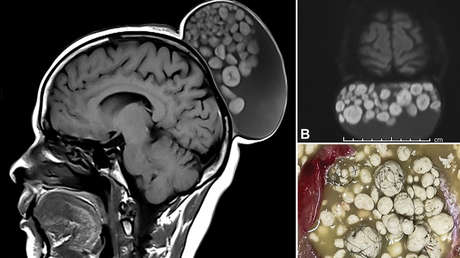

Un equipo médico dirigido por los neurocirujanos Sumit Thakar y Pavan Vasoya, del Instituto Sri Sathya Sai de Ciencias Médicas Superiores (India), extirparon un bulto en la cabeza de una mujer de 52 años que se encontraba lleno de bolas blancas como si fuese un "saco de canicas". En un informe publicado recientemente en la revista Radiology, los autores detallaron que la protuberancia estaba creciendo en el cuero cabelludo de la mujer desde su infancia.

Un teratoma quístico maduro

Después de completar la escisión quirúrgica, los doctores observaron que el quiste contenía material similar al sebo, esférulas duras y múltiples mechones de cabello flotando dentro de una matriz líquida. Un examen histopatológico confirmó el diagnóstico de un teratoma quístico maduro, con elementos de las tres capas germinales (embrionarios). Los especialistas controlaron la evolución de la mujer durante seis meses luego de la extracción del quiste y comprobaron que no se presentó una recurrencia.